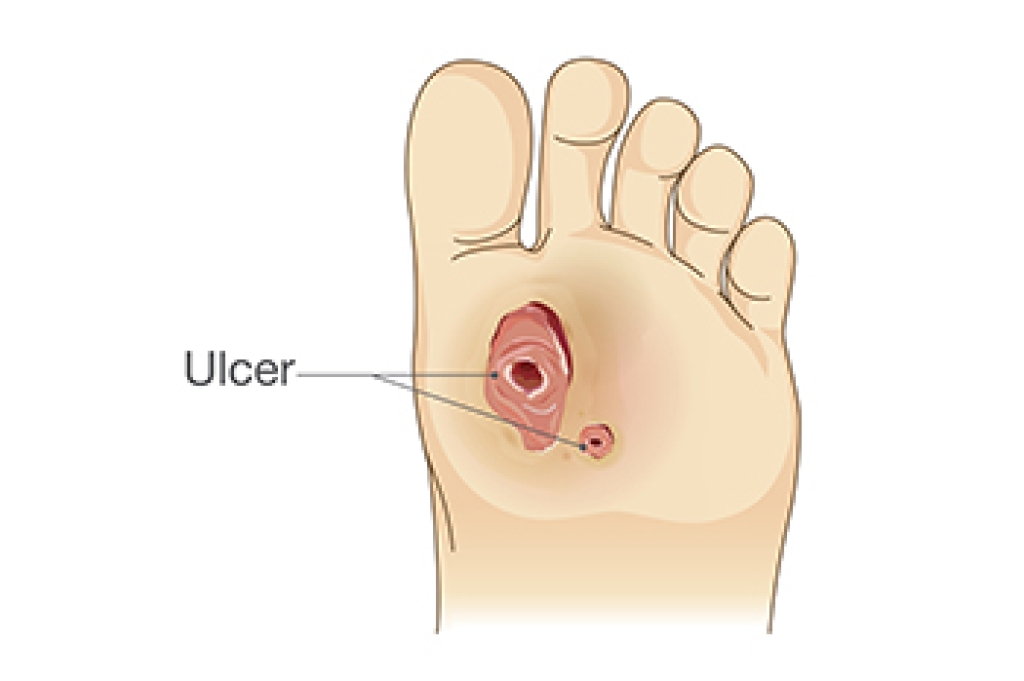

Different Types of Diabetic Foot Ulcers

Diabetic foot ulcers, a major complication for individuals with diabetes, vary based on depth, infection, and location. They are primarily categorized into neuropathic, ischemic, and neuroischemic ulcers. Neuropathic ulcers occur due to nerve damage, resulting in loss of sensation in the feet. Patients may not feel minor injuries, leading to ulcers, generally located under the foot's high-pressure areas. Ischemic ulcers stem from poor blood circulation, often associated with peripheral arterial disease. They can appear anywhere on the foot but are typically found in areas with poor blood supply. Neuroischemic ulcers combine the features of both neuropathic and ischemic ulcers, presenting a blend of circulation issues and nerve damage. These are the most common and challenging to treat, as they are prone to infection and slow healing. If you are diabetic and have foot problems, it is strongly suggested that you schedule regular appointments with a podiatrist to have your feet properly examined and ensure that any brewing issues, such as foot ulcers, are treated promptly.

Diabetic foot care is important in preventing foot ailments such as ulcers. If you are suffering from diabetes or have any other concerns about your feet, contact Edward Orman, DPM from Honeygo Podiatry. Our doctor can provide the care you need to keep you pain-free and on your feet.

Diabetic Foot Care

Diabetes affects millions of people every year. The condition can damage blood vessels in many parts of the body, especially the feet. Because of this, taking care of your feet is essential if you have diabetes, and having a podiatrist help monitor your foot health is highly recommended.

The Importance of Caring for Your Feet

- Routinely inspect your feet for bruises or sores.

- Wear socks that fit your feet comfortably.

- Wear comfortable shoes that provide adequate support.

Patients with diabetes should have their doctor monitor their blood levels, as blood sugar levels play such a huge role in diabetic care. Monitoring these levels on a regular basis is highly advised.

It is always best to inform your healthcare professional of any concerns you may have regarding your feet, especially for diabetic patients. Early treatment and routine foot examinations are keys to maintaining proper health, especially because severe complications can arise if proper treatment is not applied.

If you have any questions, please feel free to contact our offices located in Perry Hall, and Fallston, MD . We offer the newest diagnostic and treatment technologies for all your foot care needs.